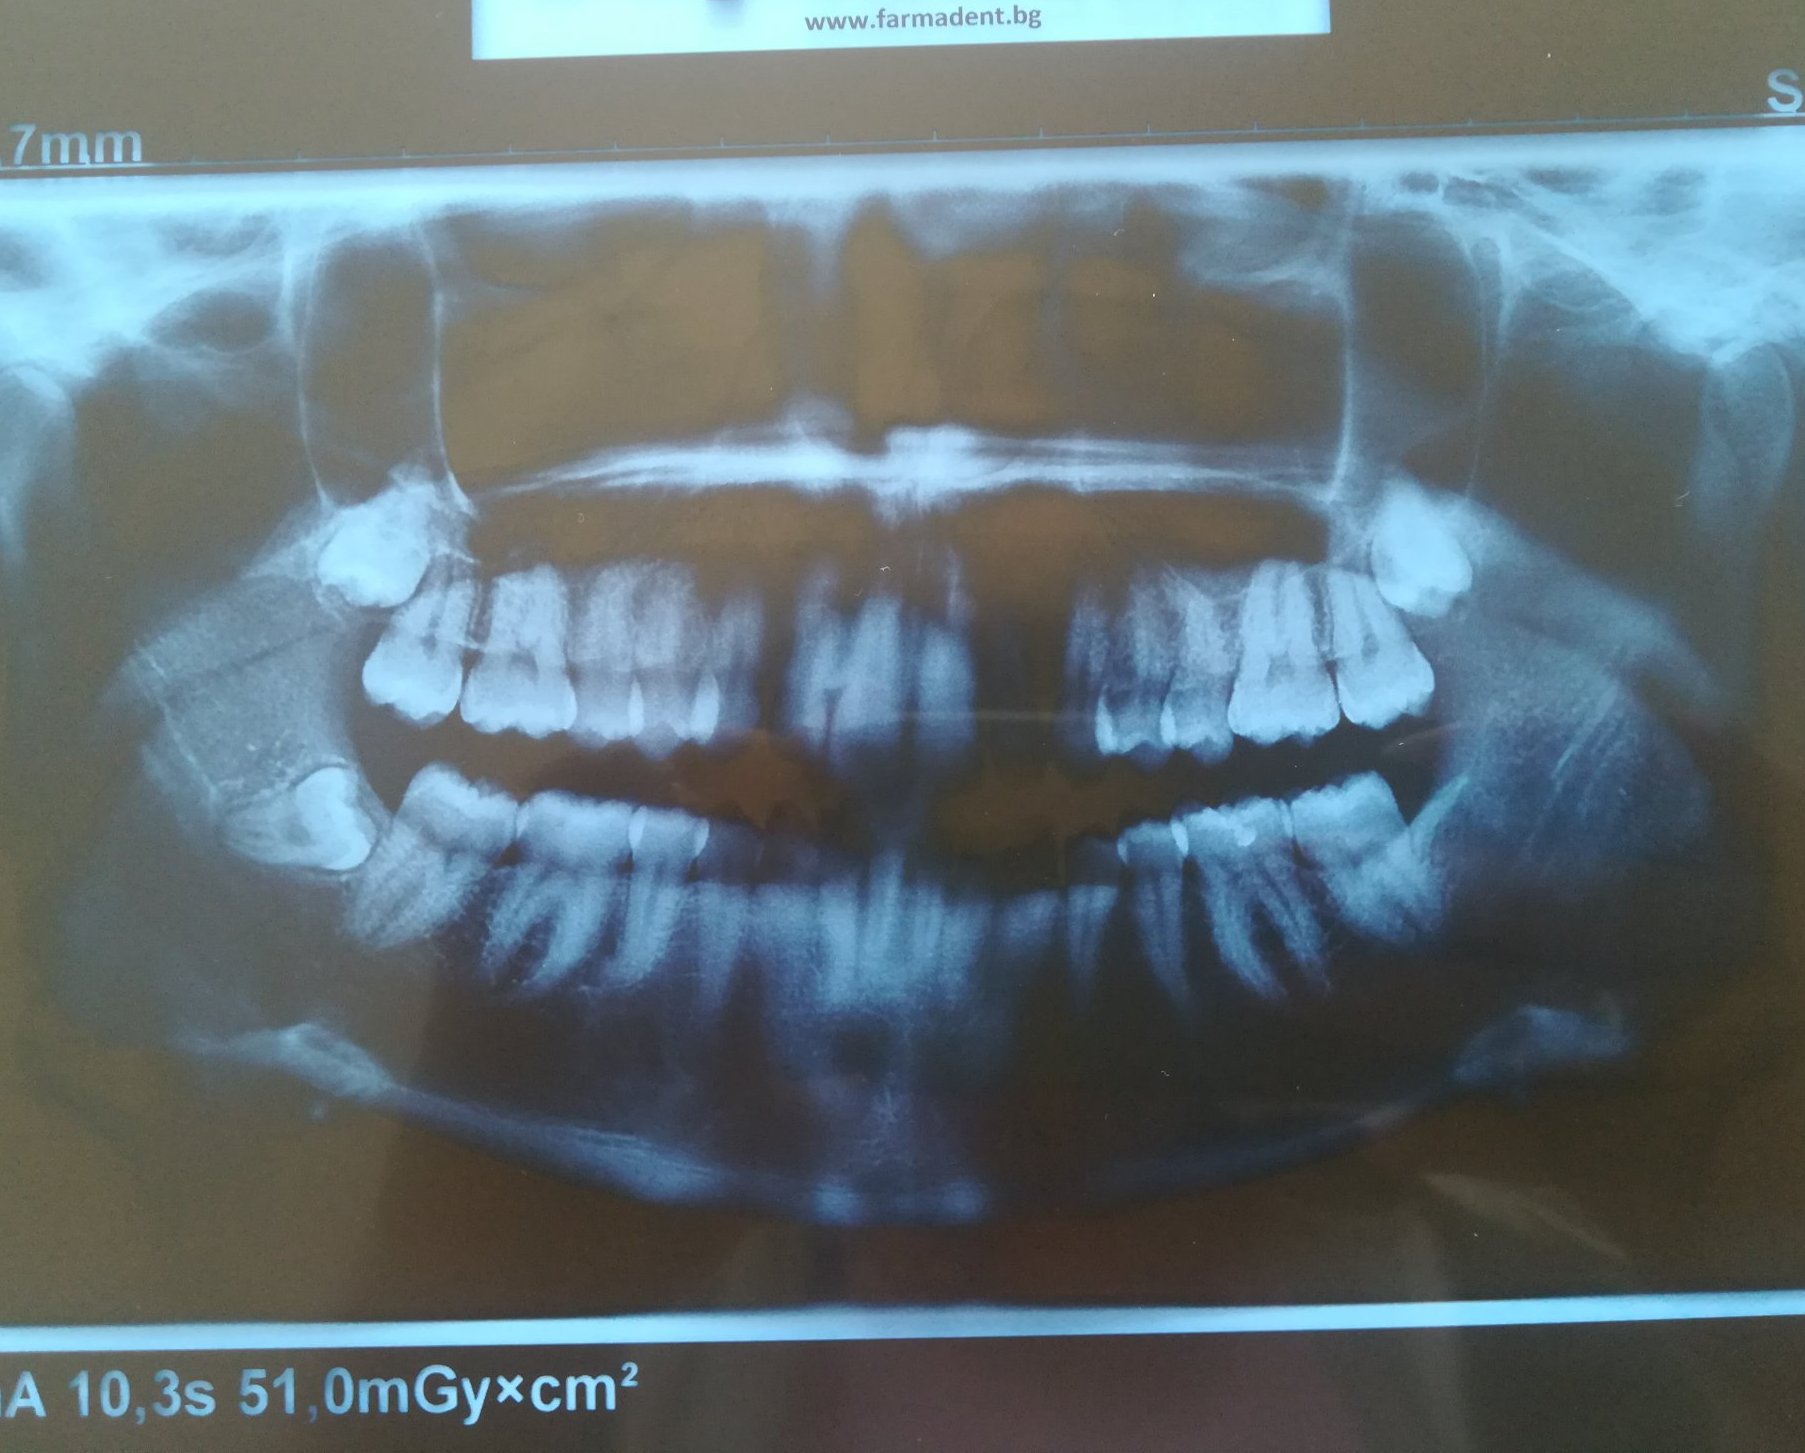

Здравейте, моя въпрос е насочен към зъболекарите от форума. Става въпрос за долен десен мъдрец който расте накриво, болка въе венеца няма или в съседните зъби, болката е под ухото и в края на челюстта(усещам нещо като напрежение, подут лимфен възел, зачервено гърло и сливица (без болка), кръвна картина която показва някакъв възпалителен процес. Ходих на Унг който ми каза класическо зачервено гърло и ми изписа хапчета,за момента никакъв ефект. Реших да отида и на зъболекар, направихме снимка и  се видя че ми растът мъдреци, отидох и на ортодонт хирург да ги види тези мъдреци и специално този долен десен защото той е криво растящия, но ми казаха че проблема ми не е от него, не се виждало възпаление и да си търся проблема в гърлото. Като цяло вече един месец се въртя в омагьосан кръг и никой не знае от къде идват тези симптоми и не знам какъв лекар да търся . Ще прикача и снимката за да я видите и да споделите мнение.Благодаря предварително.